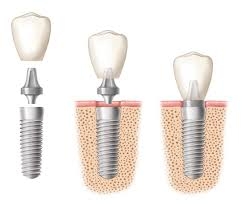

Cắm ghép răng (Implant)

Một giải pháp tối ưu cho những người bị mất răng.Thông thường khi bị mất 1 răng thì...

Khớp cắn cho implant

Khớp cắn có vai trò rất quan trọng trong chuyên ngành Răng Hàm Mặt nói chung trong đó...

Chăm sóc sau cấy ghép implant

Implant nha khoa ngày nay đang dần dần trở thành một khái niệm quen thuộc với các bệnh...